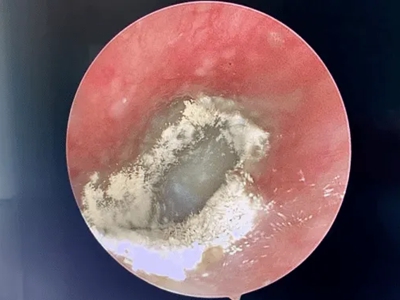

外耳道炎耳朵里有脓性分泌物图

外耳道炎患者的外耳道黏膜潮红,伴随有肿胀感,并且附着大块黄白色脓痂,形状不规则,脓痂上有白色细密鳞屑,患者自觉耳部疼痛。